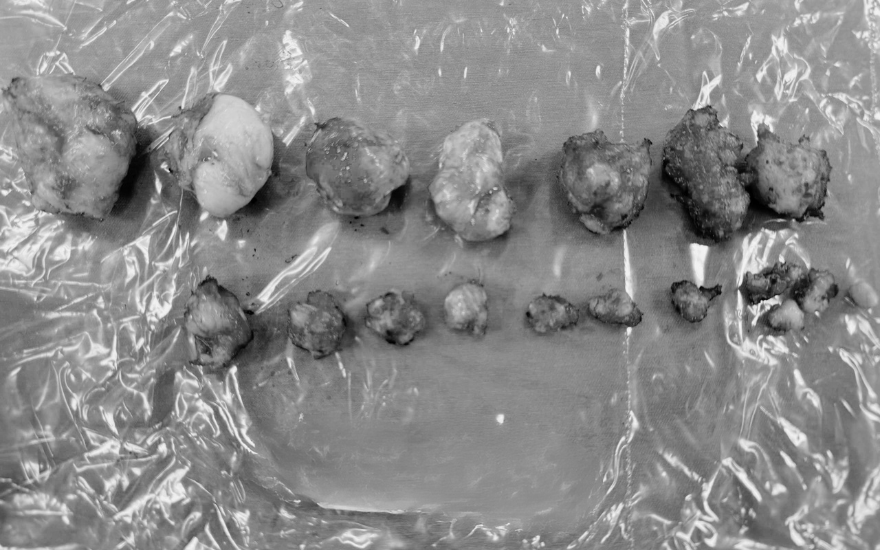

Nhờ tay nghề vững vàng của các bác sĩ, ca mổ diễn ra thuận lợi. Tổng cộng 18 khối u xơ với kích thước và độ ăn sâu khác nhau được bóc tách hoàn toàn. Tử cung và các cơ quan lân cận được bảo tồn nguyên vẹn, giữ lại khả năng sinh sản cho bệnh nhân.

18 khối u xơ được bóc tách với khối lớn nhất hơn 4cm.